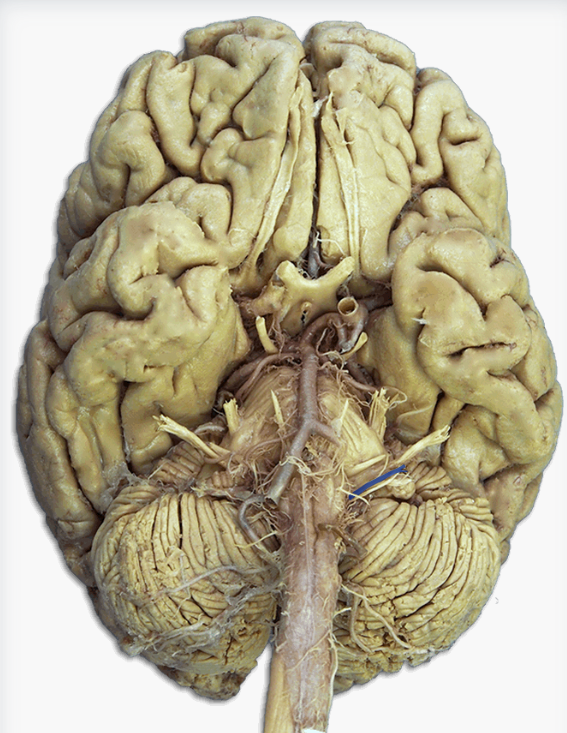

Label this cranial nerve

Olfactory (CN I) nerve

Label this cranial nerve

Optic (CN II) nerve

Label this cranial nerve

Oculomotor (CN III) nerve

Label this cranial nerve

Trochlear (CN IV) nerve

Label this cranial nerve

Trigeminal (CN V) nerve

Label this cranial nerve

Abducens (CN VI) nerve

Label this cranial nerve

Facial (CN VII) nerve

Label this cranial nerve

Vestibulocochlear (VIII) nerve

Label this cranial nerve

Glossopharyngeal (CN IX) nerve

Label this cranial nerve

Vagus (CN X) nerve

Label this cranial nerve

Accessory (CN XI) nerve

Label this cranial nerve

Hypoglossal (CN XII) nerve